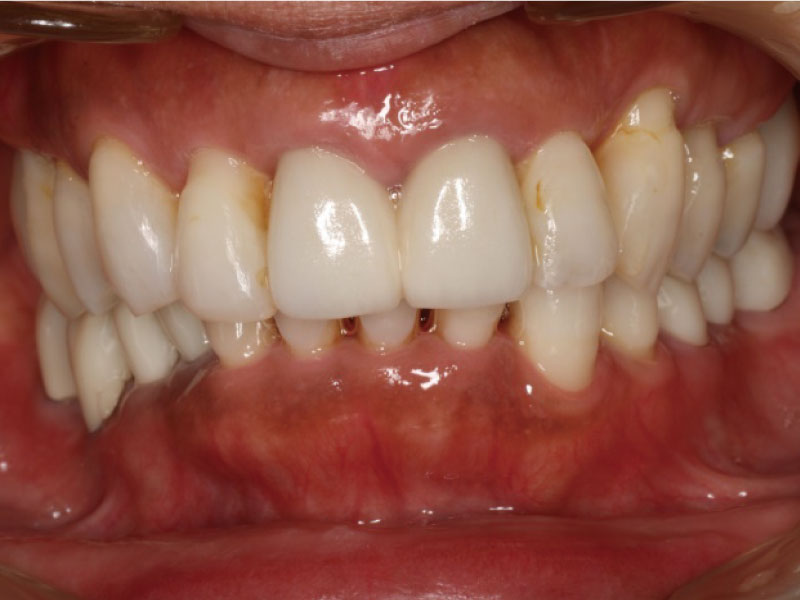

重度歯周病患者様の治療前、治療後アフター